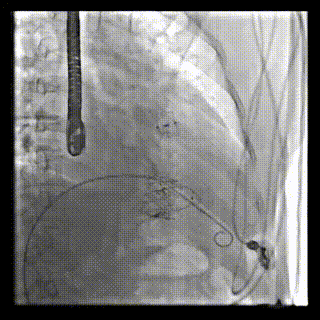

2021年12月24日,復(fù)旦大學(xué)附屬中山醫(yī)院葛均波院士團(tuán)隊(duì)成功應(yīng)用LuX-Valve Plus為一例極重度三尖瓣反流(TR)合并房顫、房缺的患者完成了經(jīng)血管三尖瓣置換術(shù),這是在前基礎(chǔ)上,本周完成的第三例經(jīng)血管三尖瓣置換手術(shù),葛均波院士、周達(dá)新教授等與心外科魏來教授、賴顥教授,心超室的潘翠珍教授、李偉教授及麻醉科的郭克芳教授共同完成了本周手術(shù),均獲得圓滿成功!患者術(shù)后超聲顯示無TR,臨床癥狀明顯改善。本周手術(shù)的成功也為LuX-Valve Plus救治性臨床研究添上了濃墨重彩的一筆。

本周三例接受LuX-Valve Plus經(jīng)血管三尖瓣置換術(shù)的患者中,第一例患者為冠狀動(dòng)脈旁路移植術(shù)+Bentall+二尖瓣成形術(shù)后;第二例患者為永久起搏器植入術(shù)后,存在跨三尖瓣導(dǎo)線;第三例患者合并房顫、房缺及左心耳封堵術(shù)后。

三例患者入院后,葛均波院士團(tuán)隊(duì)周達(dá)新教授、潘文志教授、張?jiān)床┦俊㈥惿┦考靶某业呐舜湔浣淌?、李偉教?/strong>對(duì)患者的情況進(jìn)行詳細(xì)評(píng)估和討論,最終決定為三例患者選擇LuX-Valve Plus40mm、50mm和50mm型號(hào)的瓣膜進(jìn)行手術(shù)治療。手術(shù)后即刻拔除氣管插管,術(shù)后患者三尖瓣反流癥狀得到顯著改善,復(fù)查心超結(jié)果顯示人工三尖瓣瓣膜支架固定穩(wěn)定,瓣葉關(guān)閉形態(tài)未見異常,未見明顯反流。